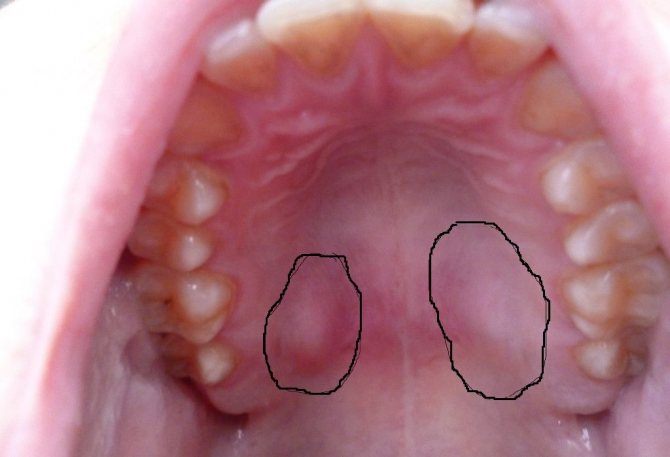

Фото характерных признаков ангиомы

Ангиома – опухоль на небе, вызванная нарушением процессов в тканях кровеносных сосудов мягкого неба. Форма шишечки напоминает свернутый штопор. Бугорок обладает синим либо багрово-черным, характерным окрасом. Шарик является продуктом нарушения развития кровеносных сосудов, поэтому цвет вызван избыточным количеством крови в образовании.

Надавливание вызывает кровотечение, экспериментировать с которым не нужно. Присутствует пульсирующая реакция на нажатие.

Подобная шишка на верхнем небе опасна для жизни пациента. Кровотечение сложно остановить, а большая потеря крови приводит к летальному исходу.

При первых признаках такого уплотнения необходимо обратится за квалифицированной помощью.